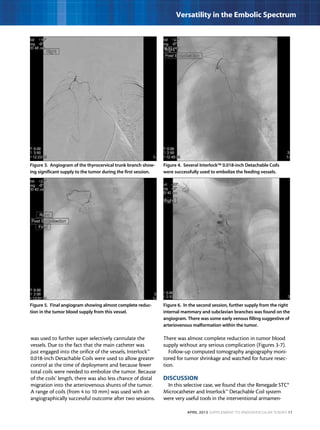

Figure 3. Angiogram of the thyrocervical trunk branch show-

ing significant supply to the tumor during the first session.

Figure 5. Final angiogram showing almost complete reduc-

tion in the tumor blood supply from this vessel.

Figure 4. Several Interlock™ 0.018-inch Detachable Coils

were successfully used to embolize the feeding vessels.

Figure 6. In the second session, further supply from the right

internal mammary and subclavian branches was found on the

angiogram. There was some early venous filling suggestive of

arteriovenous malformation within the tumor.

angiographically successful outcome after two sessions.

There was almost complete reduction in tumor blood

supply without any serious complication (Figures 3-7).